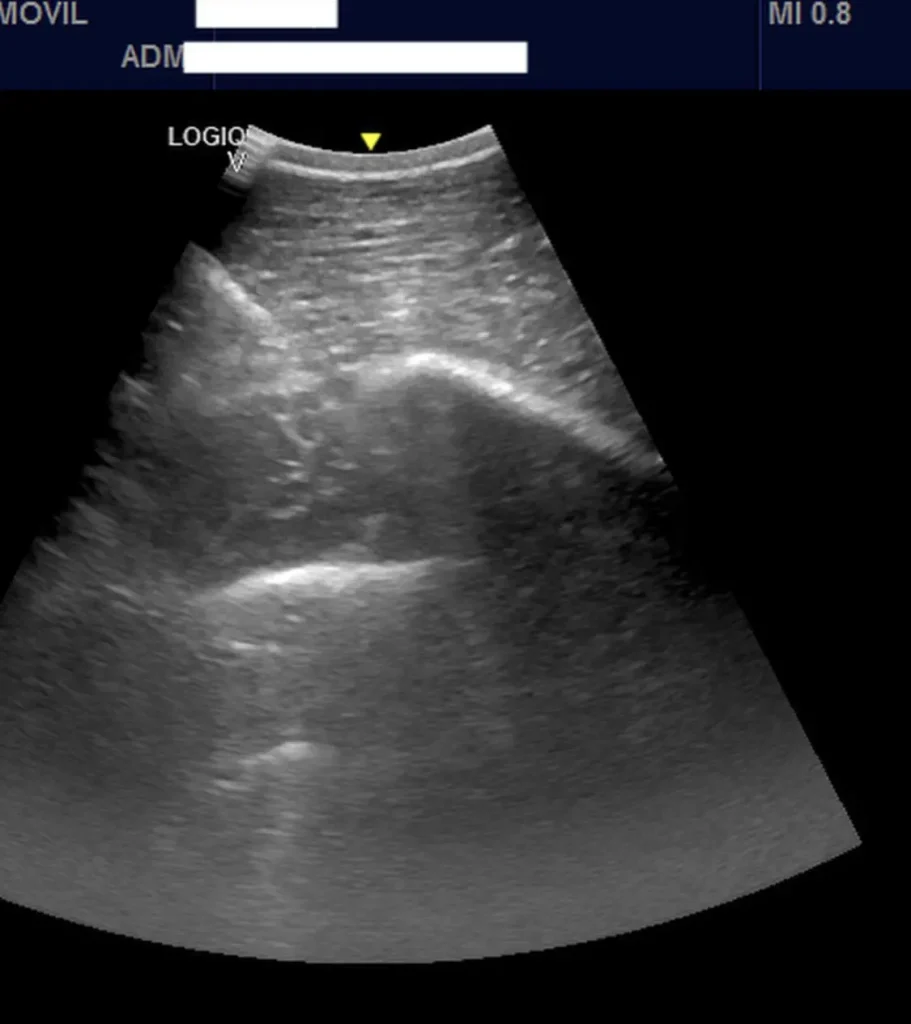

Advanced Diagnostic Imaging

We carry out diagnostic tests such as scintigraphy, magnetic resonance imaging, among others, in collaboration with equine veterinary hospitals.